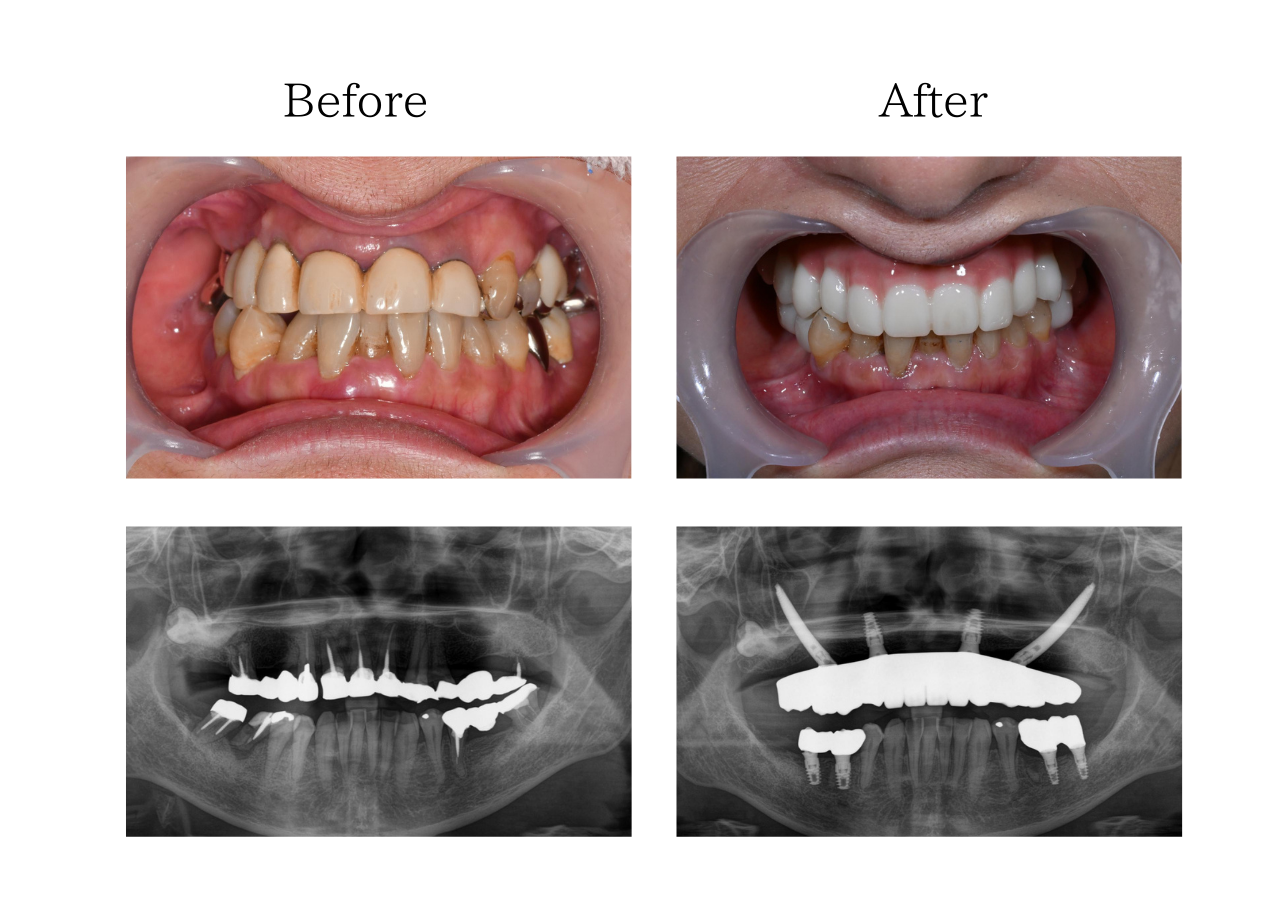

ザイゴマインプラント 体験談

※治療内容:上顎オールオン4ザイゴマ2本

下顎右下5,6左下5,6インプラント

※費用:2,859,000円*モニター価格

※期間:半年

※リスク:出血、痛み、腫れ、しびれ

「悩みを一緒に解決したい」

50代 女性 (福岡) の場合

上の歯のブリッジがかたつき始め、食べ物が噛めなくなってきました。見た目も長年気になっていて、コロナ禍のマスク生活で口元を見られることは少なくなりましたが、それと同時に人前で口元を見せることに抵抗が生まれました。ブリッジのかたつきやかみ合わせ、長年悩んできた見た目も一緒にできる治療が良いと思いオールオン4手術を決意しました。